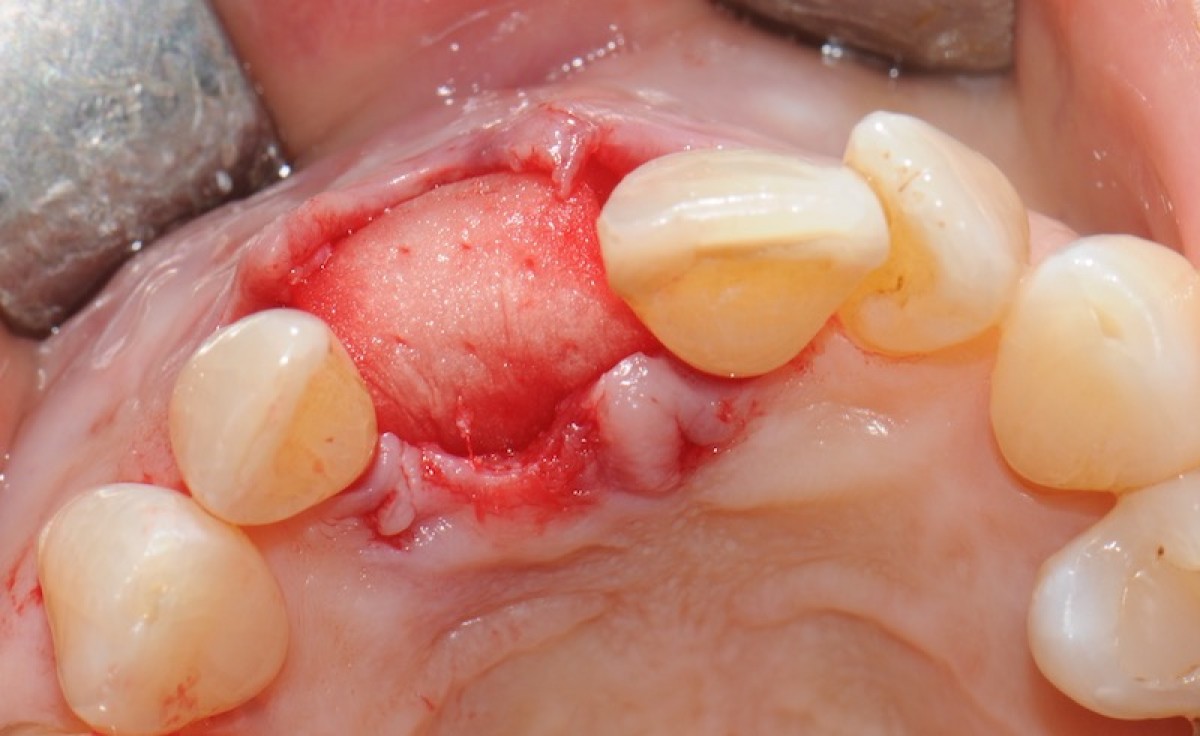

The objective of this prospective cohort study is to test the performance of a new xenogenic collagen matrix as a socket sealing material, to allow second-intention healing of post-extractive sockets filled with a xenogenic bone substitute or with an immediate submerged implant.

10 patients were recruited, presenting a single-rooted tooth scheduled for extraction. After atraumatic tooth removal, the post-extractive alveolus received either a socket preservation procedure or an immediate submerged implant. In both cases, the gingival margins of the alveolus were sealed with a xenogenic collagen matrix (Mucoderm, Botiss Dental, Zossen, Germany). The following parameters were evaluated:

• exposed surface of the matrix at the end of surgery (T0);

• the mean post-operative exposure area of the matrix was 26.25 mm2 (14.2 to 38.84 mm2 );

• 8 weeks after surgery, full wound closure was achieved in 9 out of 10 sites with healthy keratinized tissue;

• the mean colorimetric score ∆E between the regenerated site and the surrounding gingiva was 3.76 (3 to 6.55).

Seven out of 10 patients reported an excellent aesthetic integration of the matrix (∆E < 3.7).